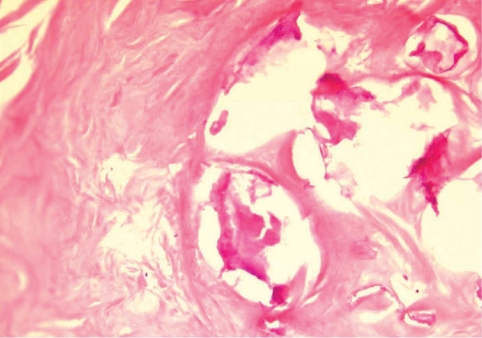

During the surgery, a small longitudinal incision was made on the upper portion of the elongated mass. A white-shiny, synovium-like piece of tissue popped out through the incision, and this was determined to be a sparganum that measured 18 cm in length and 0.5 cm in width, wriggling after removal from the patient. It was diminished to 13 cm in length and 12 mm in width after fixation in 10% formalin (Fig. 3). The calcified foci near the calf were also removed, and the pathologic examination revealed tubular tracts in the subcutaneous tissue (Fig. 4). These tracts possibly represented the pathway along which the larvae had passed. The tracks showed multiple, benign fibrocalcific nodular lesions with a few skeletal muscle fascicles, and the lesions were markedly degenerated (Fig. 5). The patient was a farmer, and she denied ingesting snake or frog meat, but she admitted drinking untreated mineral water from a local mountain. On the third postoperative day, the patient was discharged and followed up uneventfully.